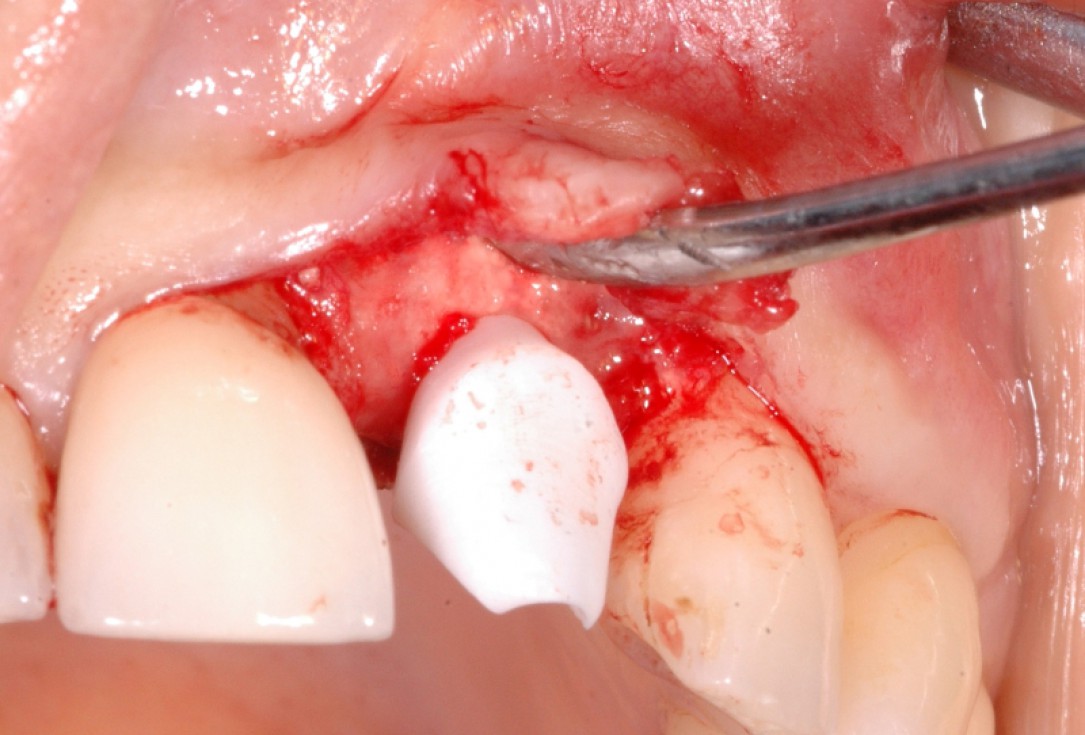

13/18 - Further soft tissue augmentation with mucoderm®GBR together with soft tissue augmentation with mucoderm® and maxresorb® - Dr. S. Scherg